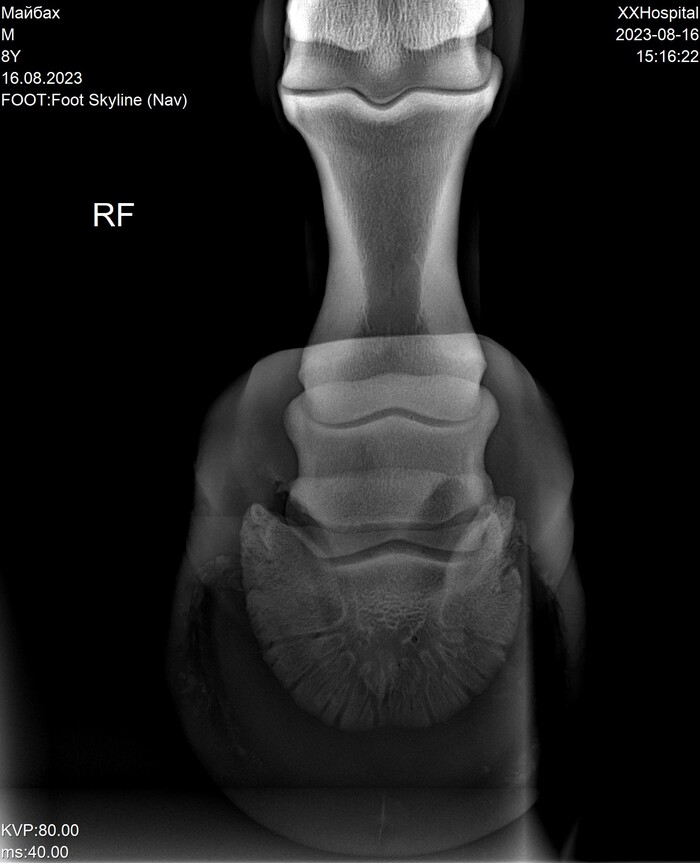

На этих x-ray снимках Домбай.

У него артроз (или артрит, я такой себе врач) пальчиков на руках.

Плюс косточка в копыте подходит очень близко к краю.